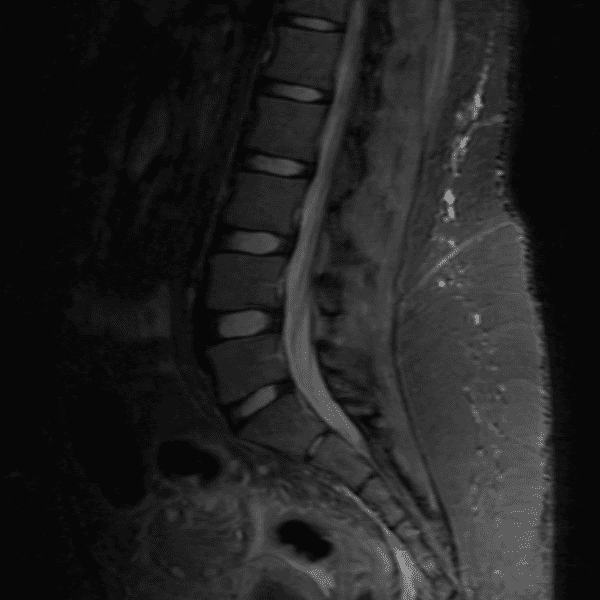

Simulates call by including subtle or difficult cases and some normals.

35 cases